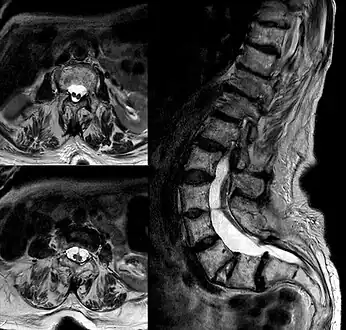

- Diastematomelia in MRI of lumbar spine.